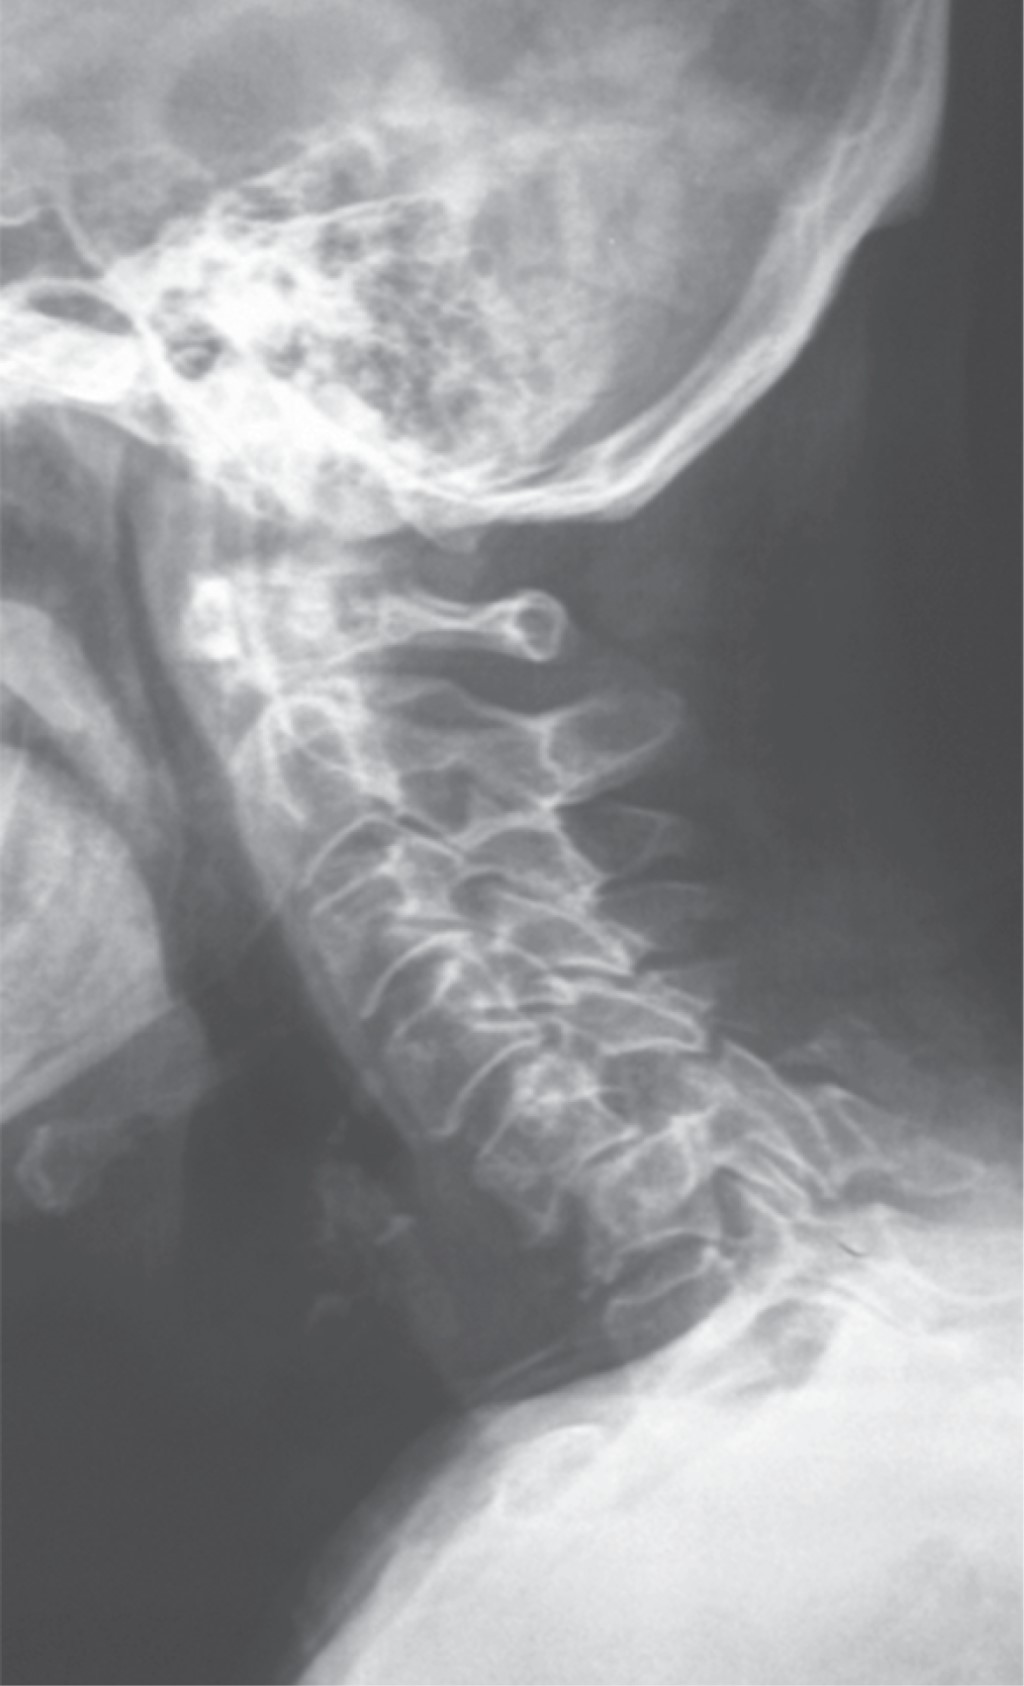

Subaxial cervical spine luxation is a frequent entity in polytraumatized patients, regularly accompanied by neurological injuries such as paraplegia or quadriplegia, requiring urgent surgical treatment in order to stabilize, align and decompress the nerve structures, sometimes it is not possible to perform this type of procedure early due to the general conditions of the patient or the conditions of the hospital units, leading to a late treatment, however, undiagnosed luxation occur, or in the worst case scenario, an inadequately treated injury with poor results that lead to an unsatisfactory evolution of the patient, with chronic pain and neurological deficit. We analyze the case of a patient with subaxial cervical spine luxation, with torpid evolution, requiring a new intervention two years after her injury, performed in three specific sequential times, achieving the patient's recovery and motor functionality.REFERENCES